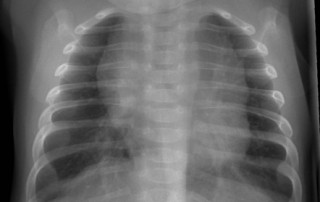

Bronquiolitis, medicamentos que vuelven a recomendarse

En 2014, la Academia Americana de Pediatría (AAP) estableció guías contra el uso de los siguientes medicamentos nebulizados en la bronquiolitis.

• Salbutamol

• Adrenalina racémica

• Suero hipertónico

Pero a pesar de las recomendaciones, los médicos han seguido utilizando estos tratamientos por una respuesta beneficiosa en muchos pacientes. Las recomendaciones originales se basaron en una revisión de Cochran de 2014. La revisión posiblemente minimizó resultados […]